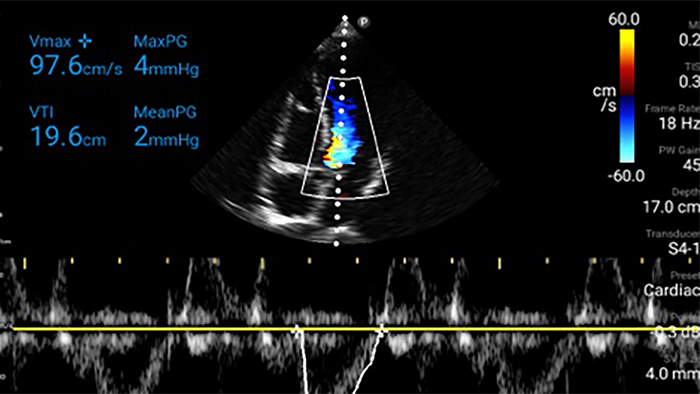

Lumify kan helpen de subtiele details van een beeld zichtbaar te maken en afwijkende weefselstructuren bloot te leggen vanuit verschillende hoeken. Hierdoor kunt u met vertrouwen realtime beslissingen nemen, van diagnose tot herstel.

Beoordeling van de functie van het linkerventrikel